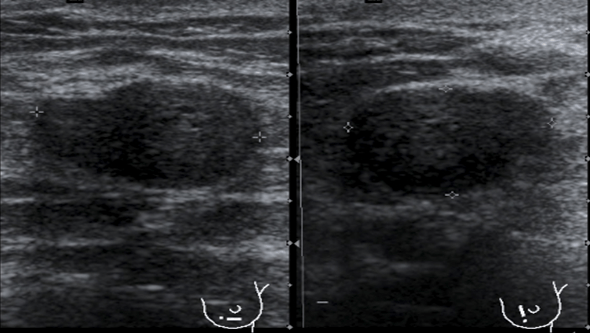

En la imagen 1 ya puedes observar la semiología típica de este tipo de tumores, homogeneidad, hipoecogenicidad y forma pseudotriangular. Aquí ya nos debe llamar la atención, está muy pegado a la carótida, la anatomía adyacente está conservada, en la imagen 2 te lo marco con flechas rojas para que lo ubiques bien.

Te pido ahora que observes aténtamente la imagen 7 y la imagen 8 y en las lesiones marcadas con flechas amarillas. En la imagen 7 puedes ver imágenes nodulares en ambos lóbulos tiroideos, son nódulos de los que habitualmente encontramos en un bocio multinodular, compara ahora con la imagen de la imagen 8, así a bote pronto, ¿Te llama algo la atención?…mira bien las imágenes…tómate un momento, no sigas leyendo…

Sí, efectivamente, la lesión de la imagen 8, que es a la que le hemos estado dedicando este tiempo, parece estar localizada fuera del tiroides, en su LTD, concretamente en su porción más profunda, como pegada a él…aunque el aspecto pueda ser similar a un nódulo normal, en este caso, la localización de la lesión, también nos va a ayudar en el diagnóstico.